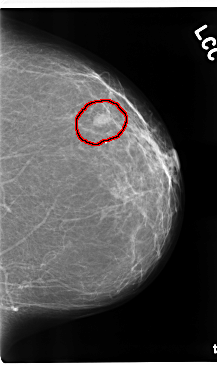

C_0210_1.LEFT_CC

FILE: C_0210_1.LEFT_CC.OVERLAY

TOTAL_ABNORMALITIES 1

ABNORMALITY 1

LESION_TYPE MASS SHAPE OVAL MARGINS MICROLOBULATED

ASSESSMENT 4

SUBTLETY 5

PATHOLOGY MALIGNANT

TOTAL_OUTLINES 1

BOUNDARY